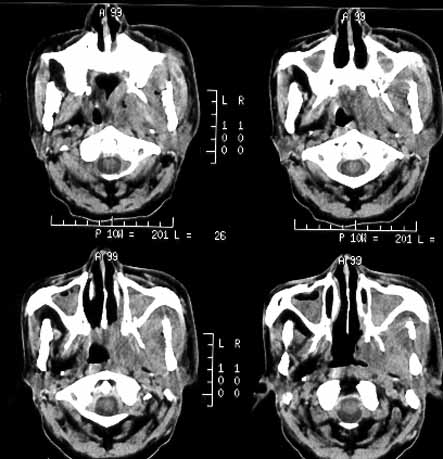

鼻咽癌06

男性,60岁,鼻咽癌放疗后12年,5年前复发再行放疗后缓解。近期牙痛,牙龈活检见鳞癌细胞。

ct诊断:鼻咽癌复发,侵及左下颌骨、上颌骨及颞下窝。